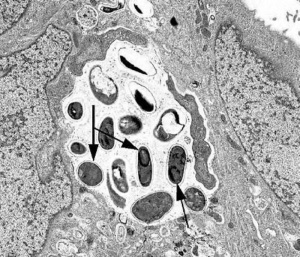

Microsporidia are obligate intracellular parasitic fungi, initially classified as protozoa.[5] Microsporidia lack typical mitochondria, thus they were initially considered to have branched prior to the endosymbiotic development of mitochondria on the evolutionary tree. This has been questioned as genetic sequencing has revealed genes coding for mitochondrial proteins and further identification of what is thought to be mitochondrial remnants within the cell ultrastructure. The complete gene sequencing of the microsporidial species Encephalitozoon cuniculi has provided significant evidence supporting the hypothesis that microsporidia are exquisitely specialized, atypical fungi that have evolutionarily lost their mitochondria while retaining mitochondria-derived organelles, referred to as mitosomes.[6][7][8] The environmentally resistant spore is the infective form of microsporidia. Infection of the host cell is achieved through the use of a specialized, coiled organelle unique to microsporidia, called the polar tubule. This structure can be demonstrated on ultrastructure visualization of the spores. Osmotic pressure changes within the spore cause the polar tube, or polar filament, to evert and extend towards the eukaryotic host cell followed by transfer of the microsporidia cellular contents (sporoplasm). Once occupying the host, the parasitic microsporidia replicates intracellularly, filling the cytoplasm. Eventually, once the spores have reached maturity, the host cell lyses and releases them into their surroundings.[4]

The gold standard for identification of microsporidia is transmission electron microscopy (TEM). TEM may also be used to identify the species of a particular organism. However, TEM is not broadly available and is impractical for routine diagnosis. It is also cost prohibitive and time consuming.[16]